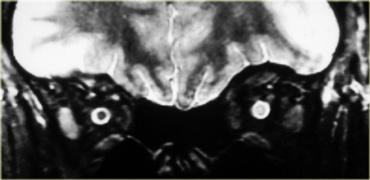

Hãy quan sát hình ảnh trước, sau đó chúng ta sẽ thảo luận chi tiết hơn.

Trên hình bên trái, thần kinh thị giác bên phải có hình ảnh bình thường.

Lưu ý rằng thần kinh thị giác là một bó chất trắng.

Nó có cùng cường độ tín hiệu với chất trắng trong não.

Ở phía đối bên, thần kinh thị giác có tín hiệu tăng cao.

Đây là tổn thương ngoài nhãn cầu trong nón cơ, và chúng ta cần nghĩ đến các bệnh lý tân sinh so với bệnh lý mất myelin.

Tiếp tục xem hình ảnh tiếp theo.Bên trái là hình ảnh chuỗi xung FLAIR kết hợp kỹ thuật ức chế mỡ (fat-sat).

Lưu ý tín hiệu bất thường và thực tế là thần kinh thị giác không bị phì đại, điều này giúp loại trừ khả năng u.Hình ảnh tủy sống cổ cho thấy một đoạn dài tổn thương không chiếm chỗ.

Dựa trên các hình ảnh này, chẩn đoán phân biệt bao gồm xơ cứng rải rác (MS) và hội chứng Devic (còn gọi là viêm tủy thị thần kinh).

Do MS phổ biến hơn nhiều, đây sẽ là chẩn đoán có khả năng nhất, nhưng trường hợp này thực tế là hội chứng Devic.Một số tác giả coi hội chứng Devic là một thể của MS, tuy nhiên hội chứng Devic khác với MS ở các điểm sau: